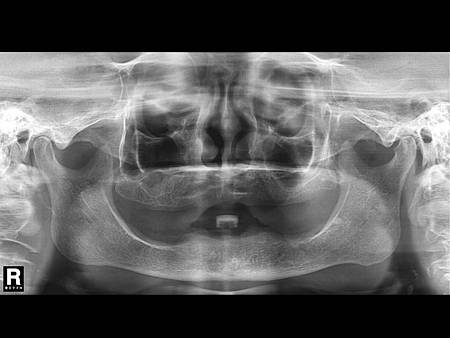

患者術前x光片

經評估後植入兩顆xive德國製人工植牙增加下顎支撐